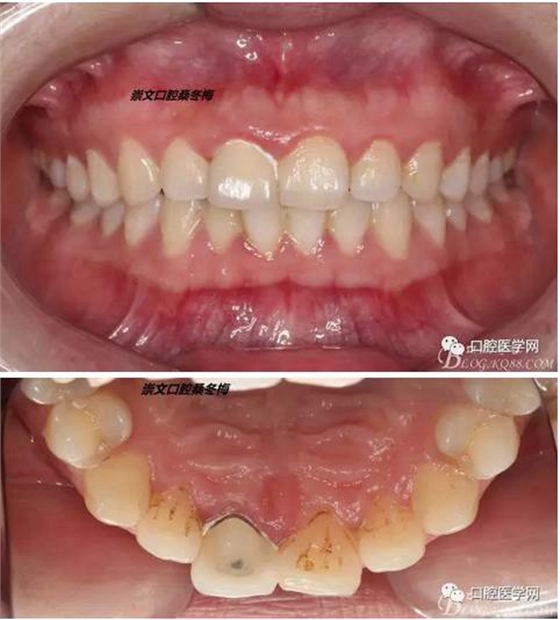

術(shù)前X線片

翻瓣 見11釉牙骨質(zhì)界存在,牙槽嵴頂?shù)接匝拦琴|(zhì)界不足2mm。21牙槽嵴頂?shù)接匝拦琴|(zhì)界不足2mm

去骨后,牙槽嵴頂?shù)接匝拦琴|(zhì)界達(dá)到2.5mm。保留11,21之間的牙槽嵴頂,不改變齦乳頭的狀態(tài)。

術(shù)后一周拆線

牙冠延長術(shù)后6周復(fù)診牙齦齦緣形態(tài)恢復(fù)良好,齦乳頭有些欠缺,患者著急永久修復(fù)。